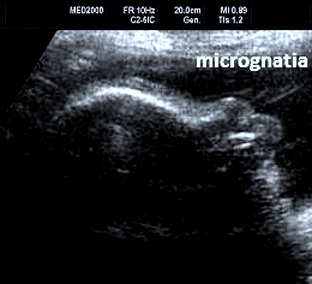

E' una displasia scheletrica caratterizzata da nanismo rizomelico con incurvamento del femore e della tibia. Si associano dismorfismo facciale (con micrognazia e palatoschisi), ipoplasia toracica  con coste corte (di solito sono presenti 11 paia di coste), ambiguità dei genitali fino al sex reversal (cariotipo maschile con fenotipo femminile); frequente è l'ipoplasia della fibula; si evidenzia inoltre piede torto, idrocefalia, macrocefalia.

Dal punto di vista diagnostico la caratteristica più importante e significativa è infatti l'incurvamento del femore e della tibia; una caratteristica unica, ricorrente nel 75% dei feti affetti, è la presenza di un cariotipo di tipo maschile con genitali ambigui o femminili.